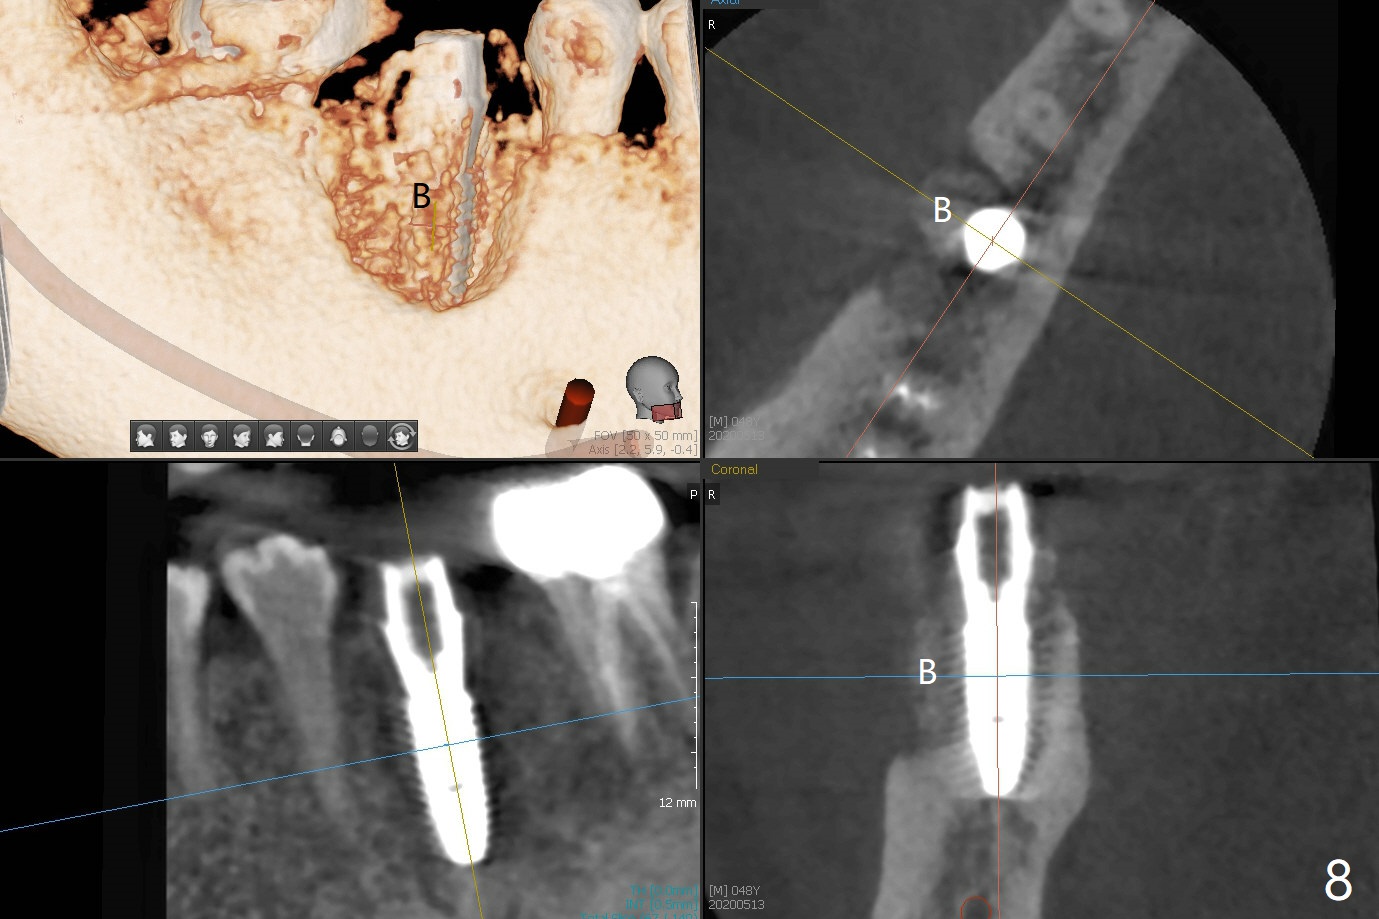

When the tooth #30 is extracted, the gingiva buccal to the septum (S in Fig.1,2 (P: papilla between the mesial and distal roots)) collapses. The latter is fixed with placement of a 4.5x11.5 mm implant (with guide), a 5.2x4(5) mm cemented abutment (Fig.3) and mixture of cortical bone (125μm – 850μm) and cortical/cancellous bone (.5-1 mm) with PRF (sticky bone, B in Fig.4-6). After placement of 2 pieces of PRF membrane over the bone graft, a temporary crown is fabricated to cover the buccal defect (Fig.7 T). Approximately 7.5 mm of the buccal threads are covered by the thick layer of bone graft (Fig.8 B). It is amazing to expect that the bone graft will turn into the buccal plate. It would be better if a narrower implant (4 instead of 4.5 mm) were placed more lingually or there were < 4 mm implant thread exposure (Fig.9). The gingiva reacts to the provisional nicely 7 days postop (Fig.10). The provisional will be removed for modification in 1 month. The patient complains of bad smell from the provisional 2 weeks postop. The provisional is removed. The distal socket (Fig.11 D) is healing, whereas the buccal bone graft (Fig.12 B) seems not have been vascularized. Pedicled flaps (I) should be transferred to cover the buccal bone graft. The margin of the provisional is polished, becomes short, and covered by periodontal dressing, which dislodges 2 days later. One week later, granulation tissue is forming apically with use of oral antibiotic and water jet (Fig.13 *). The bad smell reduces. The superficial loose bone graft changes colar and becomes detached 1 month 10 days postop. The temporary crown with the shortened buccal shelf is reseated for self cleansing or reapplication of PRF if needed (Fig.14).